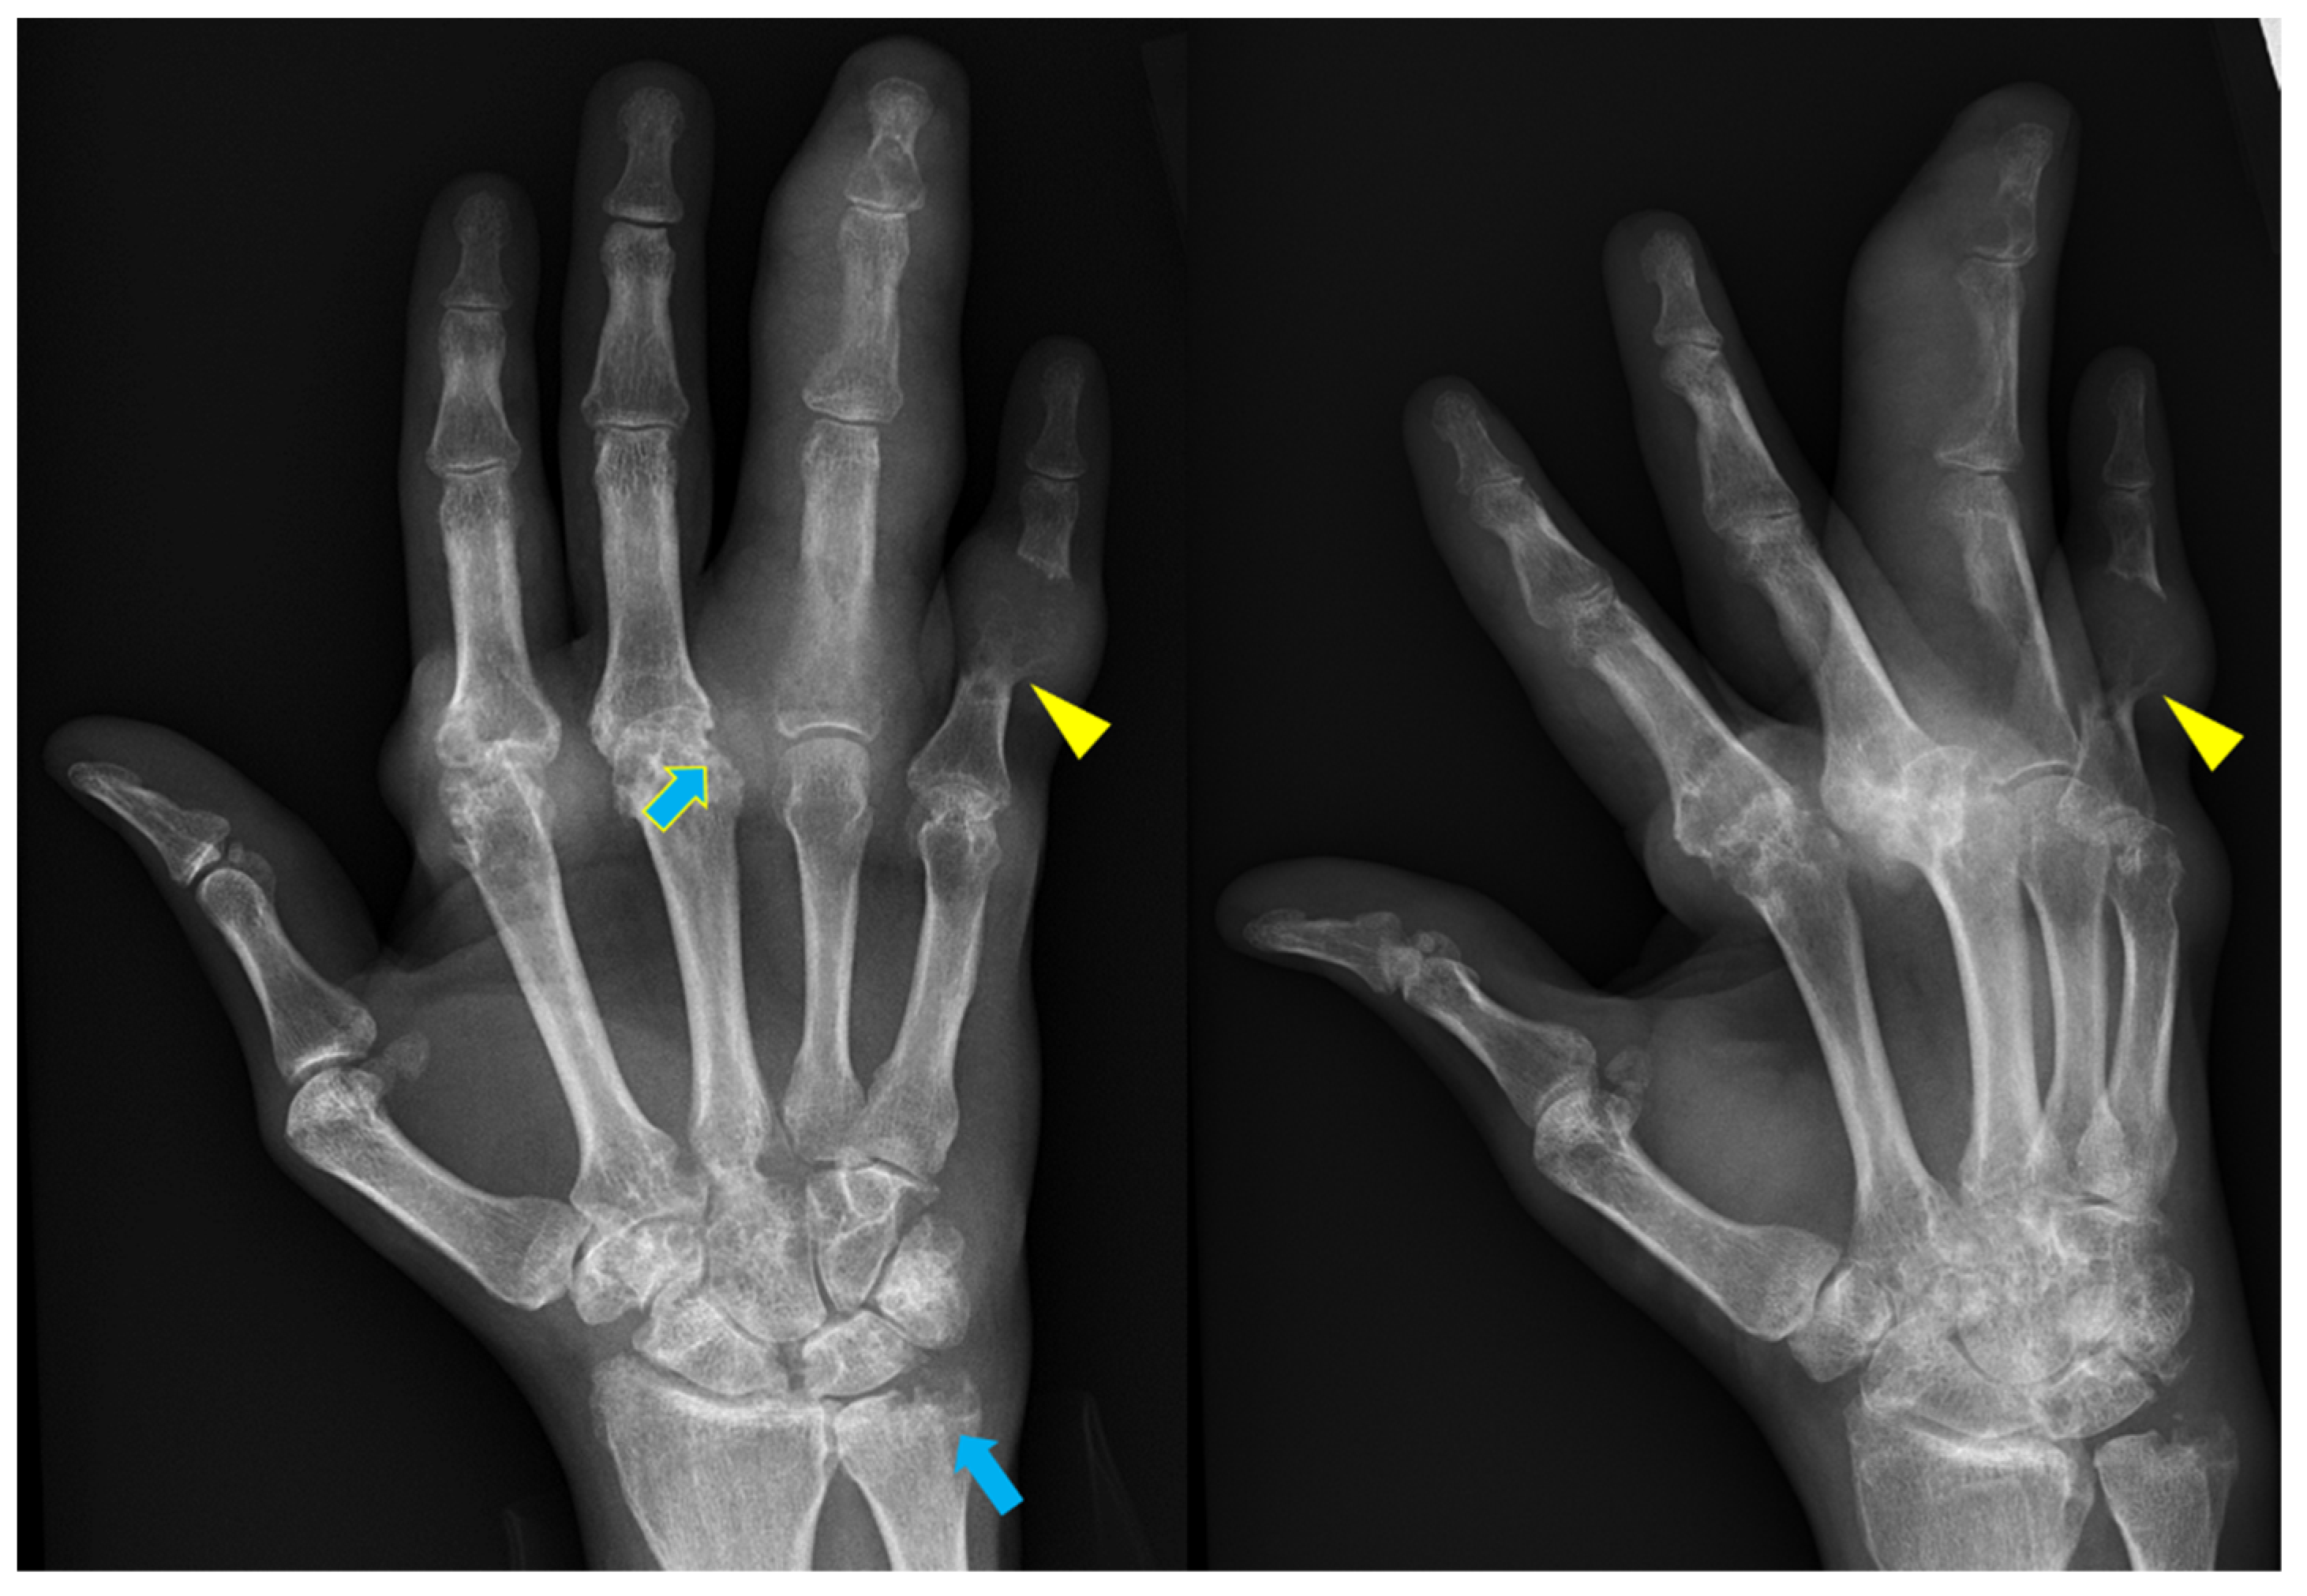

• What pathology is this

Rheumatoid arthritis

• Appearances on Xray for rheumatoid arthritis

Sever joint space narrowing

Erosions on joint spaces (Hands and feet)

Subluxation

Ankylosis (joint fusion)